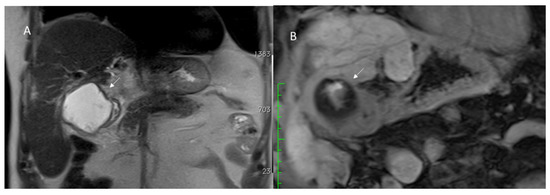

3.1.3. Vascular Thrombosis

3.1.4. Biliary Injuries